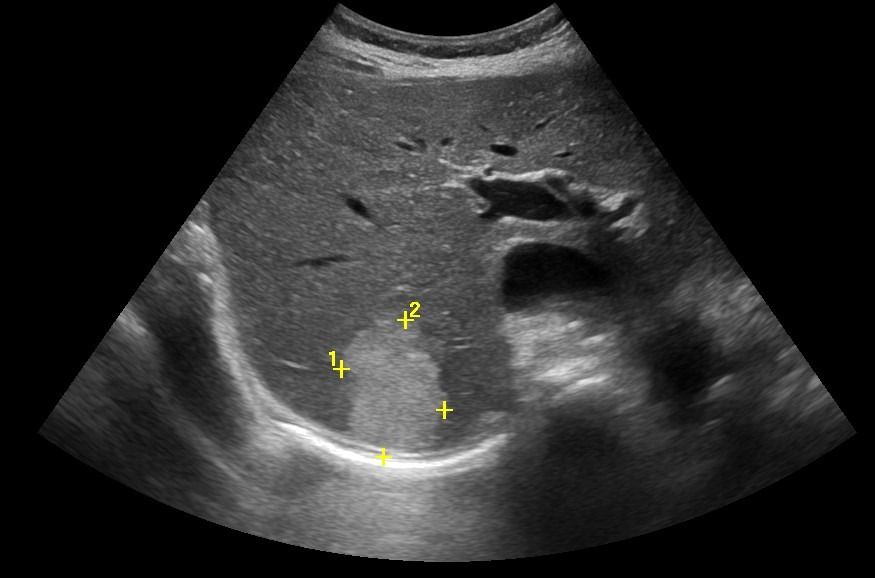

Το Yπερηχογράφημα Kάτω Kοιλίας αξιολογεί την ουροδόχο κύστη και τα έσω γεννητικά όργανα. Η πλήρωση της ουροδόχου κύστεως είναι απαραίτητη για τη διερεύνηση παθολογιών όπως:

- Λιθίαση

- Τοιχωματικές βλάβες

- Συμπαγείς βλάβες (όπως θηλώματα)

Στους άνδρες, αξιολογείται ο προστάτης, με μέτρηση των διαστάσεων και εκτίμηση του βαθμού υπερτροφίας και του κυστικού υπολείμματος μετά την ούρηση.